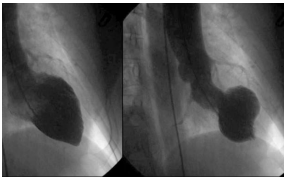

Ventriculografia a seguir:

Ecocardiograma transtorácico demonstrou acinesia apical e hipocinesia dos segmentos médios, com hipercinesia de segmentos basais, além de disfunção moderada à grave do ventrículo esquerdo.

Eletrocardiograma de admissão: ritmo sinusal; eixo QRS normal; com supradesnivelamento do segmento ST de 1mm em D1, aVF, V5 e V6.